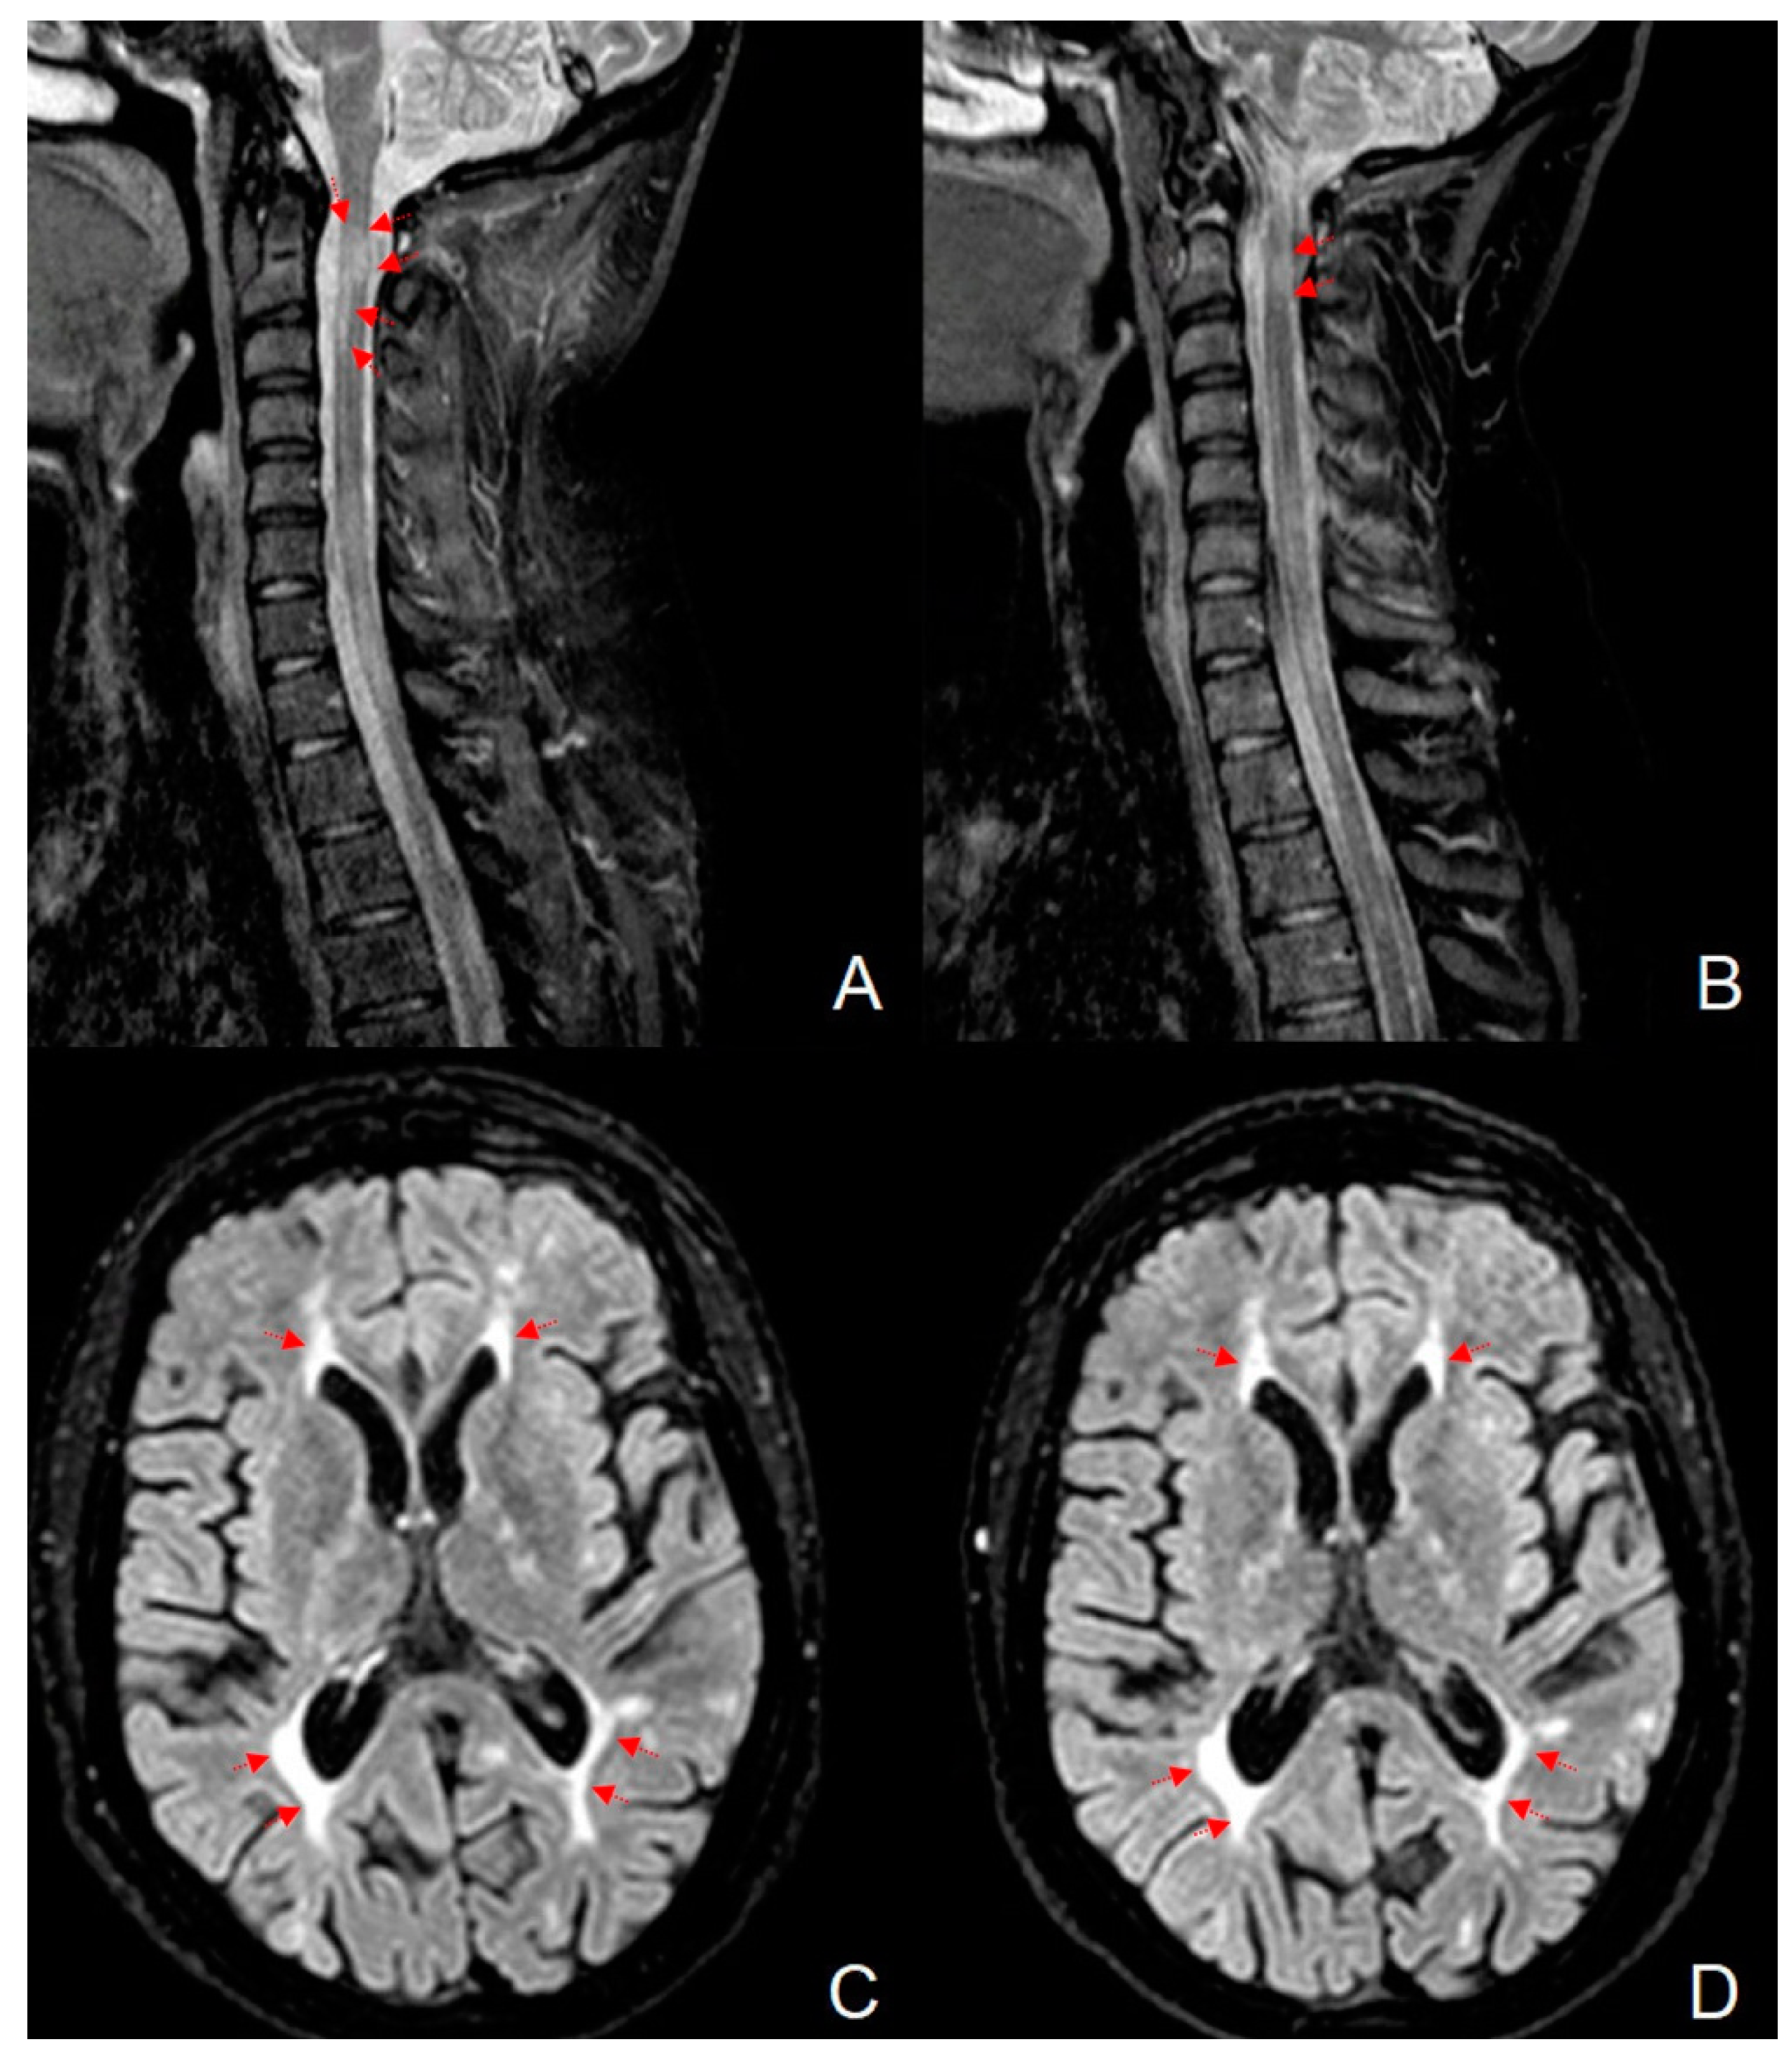

Figure 1.

Magnetic resonance imaging on the short tau inversion recovery (STIR) sequence of the cervical spinal cord, affected by a demyelinating lesion at the second and third metamer before (A) and after (B) DFPP treatment. Note the reduction in the size of the lesion in comparison to the pre-treatment image. Axial brain magnetic resonance imaging on the fluid attenuated inversion recovery (FLAIR) sequence shows the periventricular lesion load before (C) and after (D) DFPP treatment. Red arrows evidence the brain and spinal cord lesions.

These lesions, partially confluent and not exceeding three metamers in length, were not associated with tumefactive cervical shape and fulfilled the radiological criteria for MS lesions, as expected. No new brain lesions were detected and a total intracranial volume (TIV) of 1328.8 mL was calculated using Siena software. Thus, the diagnosis of steroid-refractory relapsed MS on Fingolimod treatment was posed, DFPP therapy was indicated, and FTY was discontinued. In Figure 1C it could be also glimpsed two subcortical hyperintense left frontal areas, resulting from enhancing lesions at the disease onset. The demonstration of these lesions assumes an important diagnostic role in the present case, and they are better represented in Figure 2.

The control MRI performed before the department discharge showed detectable reduction in the volume of cervical lesions, as depicted in Figure 1B, but a stable brain lesion load (Figure 1D).